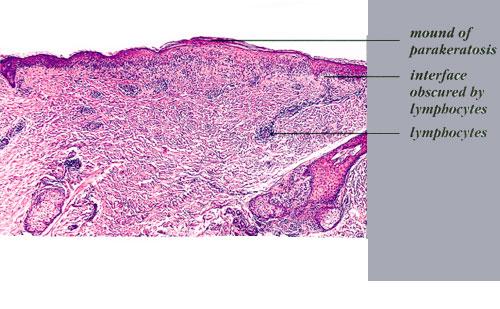

Atlas of skin histopathology

Mucha-Habermann disease = داء موشاهابرمان